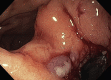

Results: Five patients (2 male, age 44-89 years) were included. Four patients had postoperative PFCs, and 1 presented with a pelvic abscess complicating acute diverticulitis. Two of 5 had fecal diversion; the remaining 3 had unaltered large-bowel anatomy. One case had a concomitant abdominal collection, treated with percutaneous drainage in the same session. An electrocautery-enhanced LAMS delivery system (15 × 10 mm) was used in all cases. EUS-TRD was performed with the direct-puncture technique and lasted less than 10 minutes in 4 cases; in the remaining case, needle puncture and LAMS placement over a guidewire was required, and the procedure length was 14 minutes. The clinical success rate was 100%. LAMSs were removed after a median of 14 (range, 12-24) days. One patient reported partial proximal LAMS migration after 24 days (mild adverse event). No PFC recurrence was observed.

Conclusion: EUS-TRD with LAMSs is a safe and effective technique for treatment of PFCs. The use of 15- × 10-mm LAMSs allows rapid PFC resolution. EUS-TRD could be performed not only in patients with fecal diversion but also in cases of unaltered anatomy.